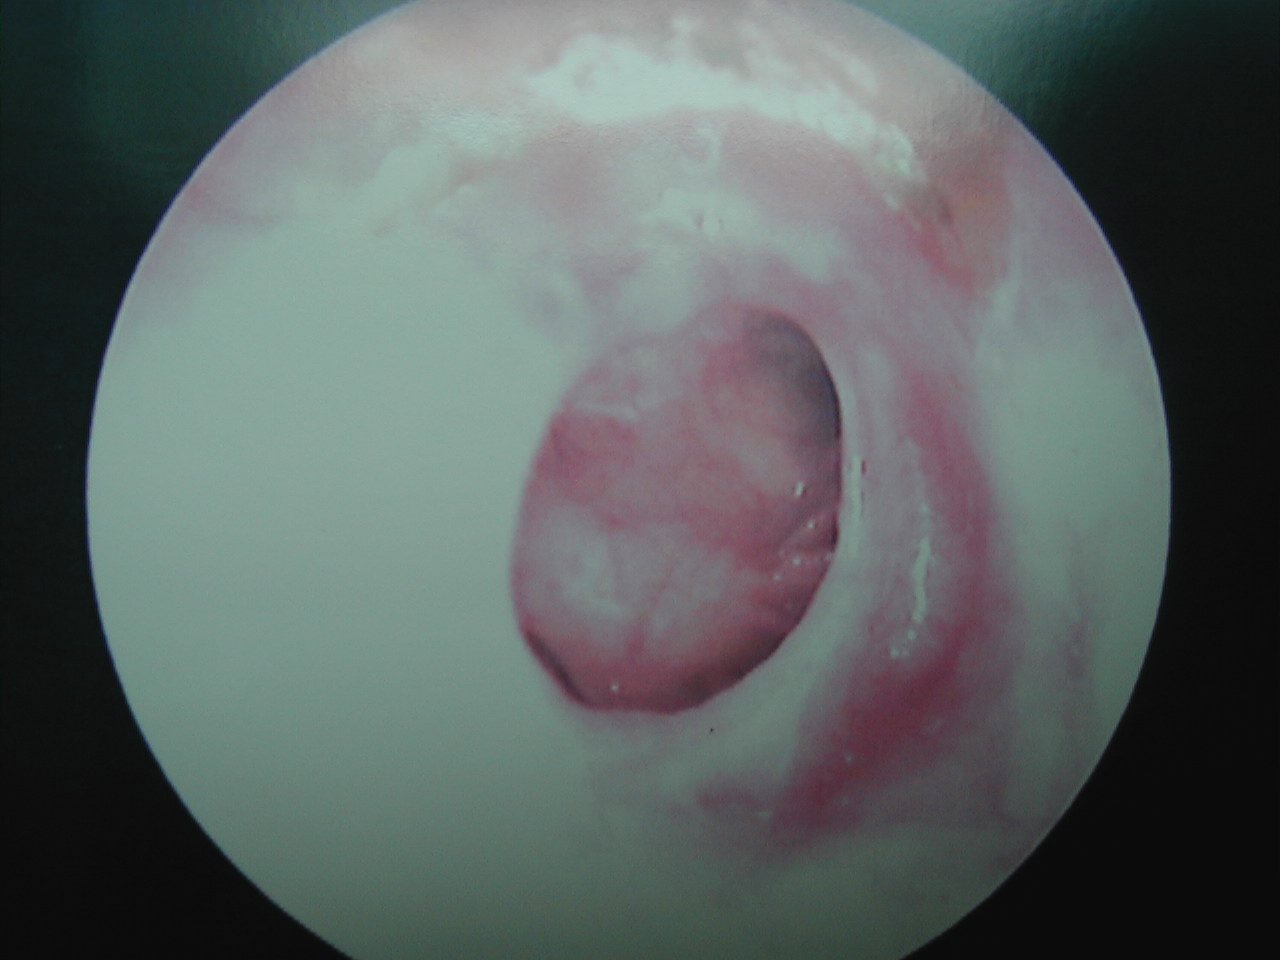

Ear tubes - The first picture shows an ear tube that has fallen out but is stuck to ear canal by ear wax. The last picture shows a T-tube, these stay in place much longer but run the risk of leaving a permanent perforation when finally removed.